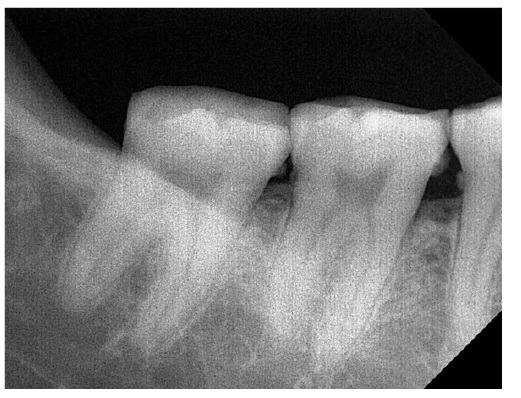

DVI is not a new discovery where identification procedures has been evolved and developed [8]. Radiology is used for a number of purposes in a mass fatality incident as it can provide information to help with the detection of foreign bodies that may pose hazard to on-site investigators, be used to uncover and pinpoint the exact location of material evidence and to aid victim identification. Although radiology has not been officially accepted to be included in the INTERPOL DVI guide, post-mortem computed tomography (PMCT) scan and X-ray have been introduced into DVI as a screening tool since 10 years ago [13]. All of the images generated from the PMCT or X-ray are digitized and kept in an electronic file for long term archiving (Figure 9). Apart from this, odontology examinations has advanced the dental imaging technology that enables the storage of dental records of the human remains made available in softcopy (Figure 10).

Figure 10. Dental Imaging (1).